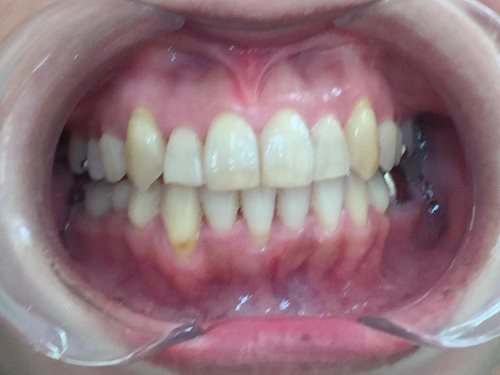

歯が綺麗に並び、見た目と噛み合わせが改善しました。

患者様にも「自信を持って笑えるようになりました」と大変ご満足いただいています。

今後、銀歯の部分を白く丈夫な「セラミック」に変えていく予定です。